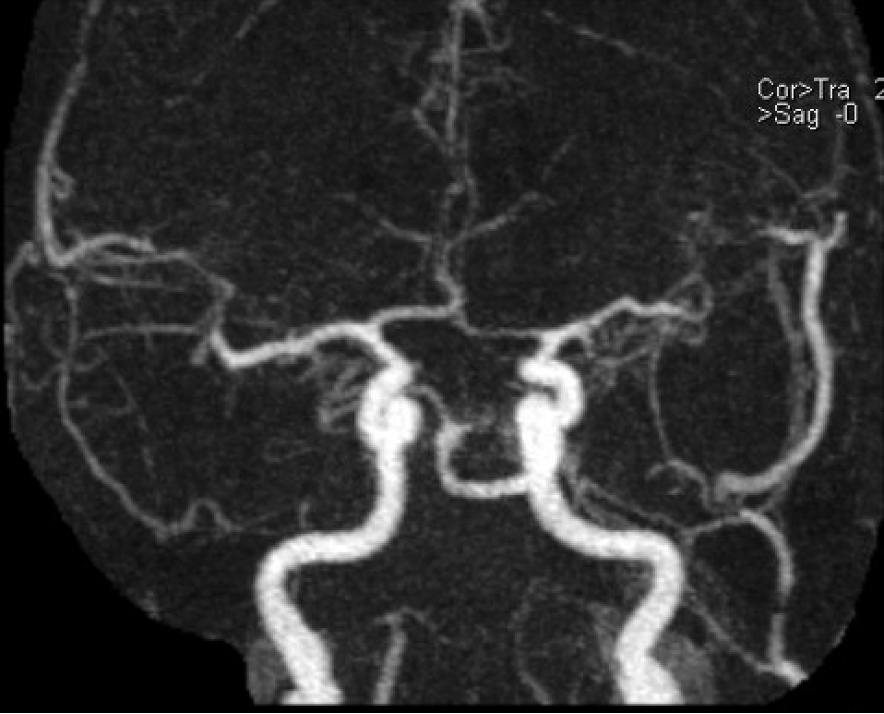

Name the three major branches off the aortic arch, as seen on this axial CTA: